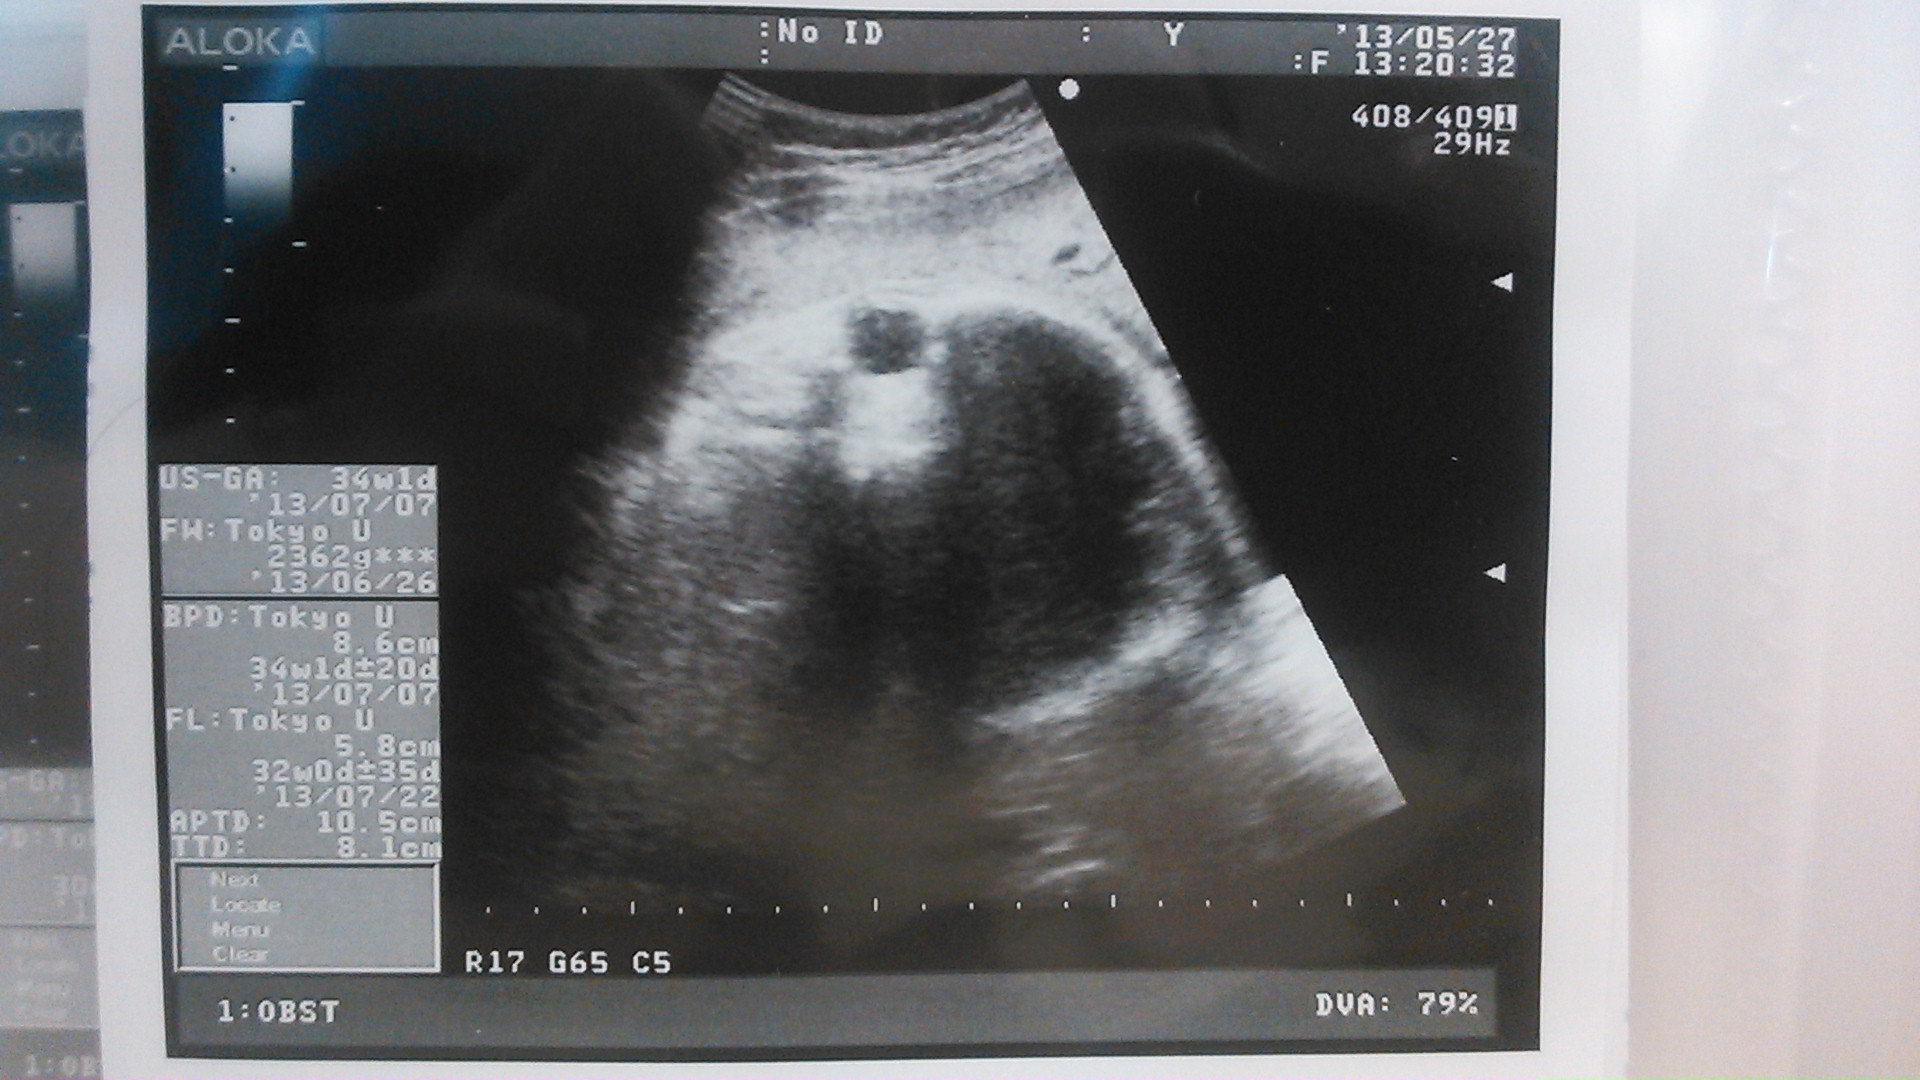

echo